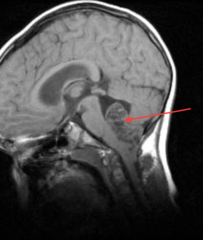

Hydrocephalus

Front

Communicating (decreased CSF absorption by arachnoid granulations) - post-meningitis scarring - Arnold-Chiaria malformation - choroid-plexus tumor overproducing CSF Non-communicating (obstructive) - foramen of monro (lateral --> 3rd) - cerebral aqueduct (3rd --> 4th) Normal pressure hydrocephalus - increased CSF and dilated ventricles BUT normal pressure - wet (incontinence), wacky (dementia), wobbly (ataxia) Hydrocephalus ex vacuo - atrophy of brain tissue leads to compensatory increase in CSF (alzheimer's, HIV, Pick)